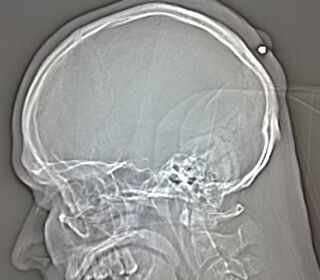

A Polish man was shot in the head five years ago. Only, he was really drunk, and didn't realize until doctors X-rayed him. This year. Think back to all the times you've been drunk: Have you maybe been shot before?